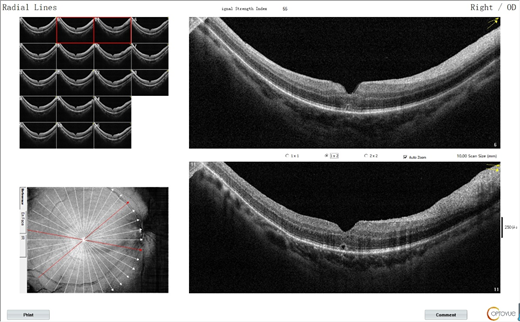

△术前黄斑OCT,黄斑裂孔明显,284μm

△手术成功,黄斑裂孔愈合

“我现在能够明显的感觉到自己的视力提升,看东西也清晰了许多,我真的很开心!”如今,李女士距离做完手术已经过去了半月有余,其视力也从术前的0.16恢复到0.5。随着视力的不断提升,她脸上的笑容也逐渐绽放了开来。因为她相信:视力会恢复得越来越来好,未来也会越来越明亮……